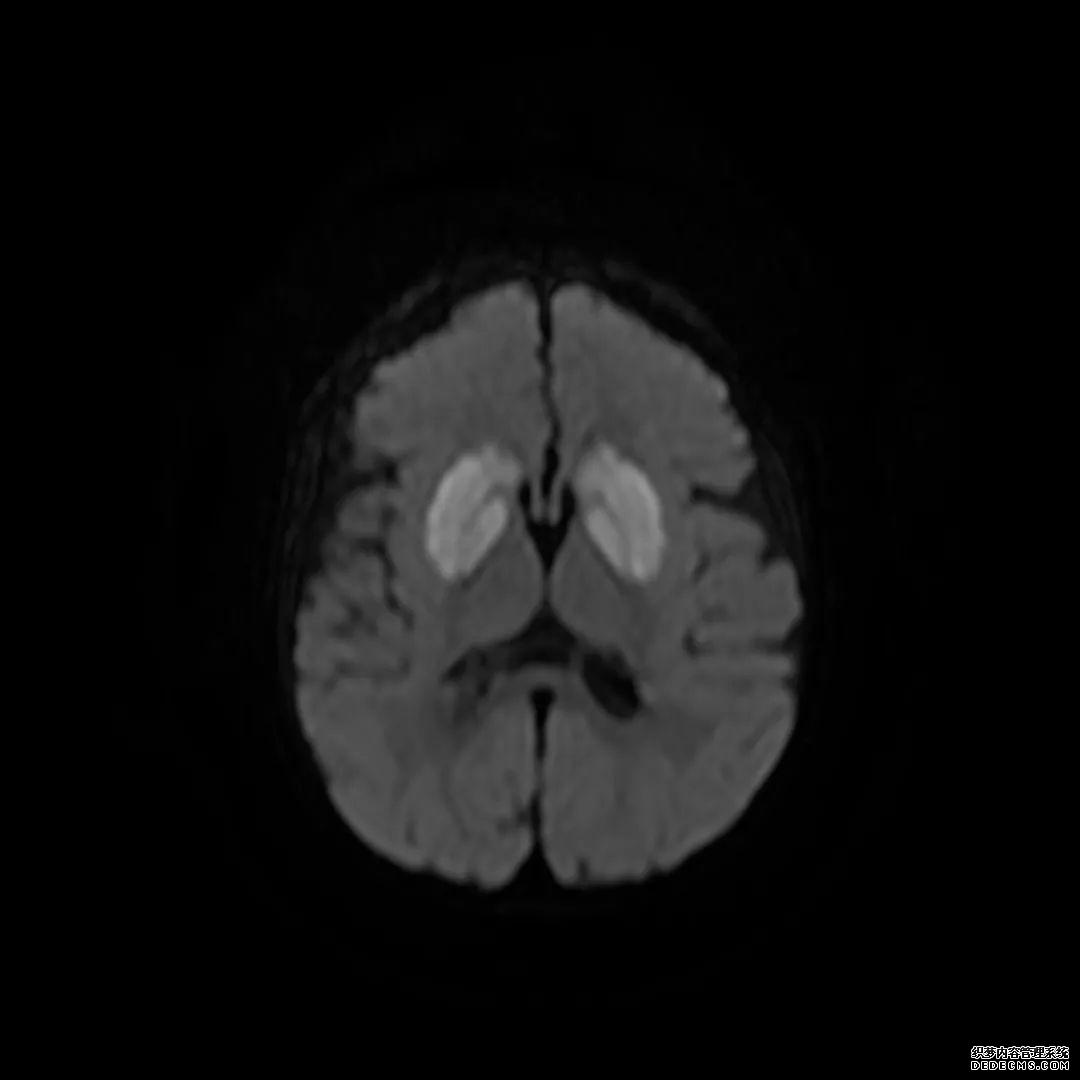

脑MRI显示尾状核、扁豆状核和脑梗头部T2/FLAIR呈双侧对称异常高信号。扩散限制涉及这些区域,其特征是扩散加权DWI(B-1000)上的高强度,ADC图上相应的减弱强度。

印象:通过将这些成像模式与临床和实验室检查结果相结合,就有可能得出低血糖性脑病。